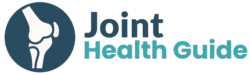

Hip pain during training is often dismissed as a minor issue. However, it may sometimes indicate a hip stress fracture — a potentially serious overuse injury that requires early recognition.

The most clinically important subtype is the femoral neck stress fracture, which affects the load-bearing region of the hip. Although relatively uncommon, delayed diagnosis can lead to fracture displacement and complications such as avascular necrosis, significantly impacting long-term outcomes.

One of the main challenges is the subtle presentation. Symptoms are often gradual and non-specific, making early diagnosis difficult in clinical and athletic settings. If left untreated, a hip stress fracture can end an athlete’s season — or career.

This article provides a clinically grounded overview of hip stress fractures, with a focus on femoral neck stress fractures, including their mechanisms, risk factors, diagnosis, and management.

- The most common presentation is exercise-related groin pain, often subtle in early stages and easily misdiagnosed.

- MRI is the gold standard for early diagnosis, as plain radiographs are frequently normal in early disease.

- Treatment is classification-driven: compression-sided injuries are often managed conservatively, while tension-sided and displaced fractures usually require surgery.

Hip stress fractures often present insidiously, which is one of the main reasons diagnosis is frequently delayed. Early symptoms are subtle and easily mistaken for more common soft tissue injuries, particularly in runners and active individuals.

In the early stage, the most typical symptom is a vague, poorly localized groin pain that appears during running or high-impact activity. Athletes often describe it as a “deep discomfort” rather than sharp pain. At this stage, symptoms usually resolve with rest, which can falsely reassure both patients and clinicians.

Diagnosis: Clinical Examination & How We Confirm Hip Stress Fracture

Because of these limitations, MRI is considered the gold standard for diagnosis. MRI can detect early bone marrow edema, which represents a stress reaction before a visible fracture develops. It also allows direct visualization of a fracture line and enables grading of injury severity, which is crucial for guiding management decisions.